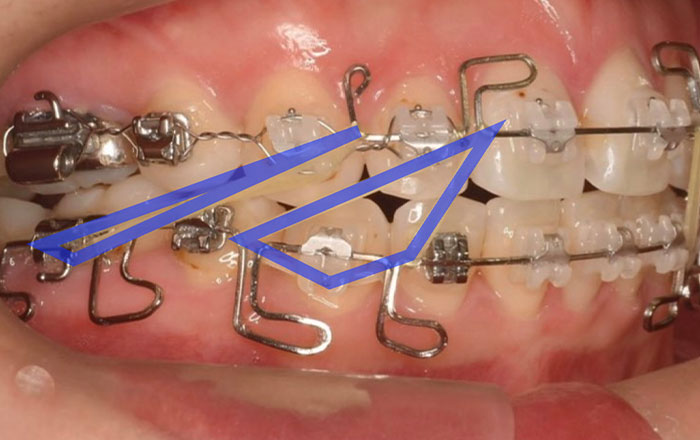

4.顎間ゴム

顎間ゴムは、矯正用の輪ゴムです。

歯を動かすため、毎日付け替えます。

ゴムの色は、歯の色に近いため、目立ちにくいです。

ゴムかけをする理由は、上下の歯の矯正器具にゴムをかけて引っ張り合う力を利用することで、噛み合わせの調整・顎のずれ改善て歯の移動を行います。

歯並びがある程度整い、噛み合わせを整える段階(矯正治療の中盤〜後半)で行います。